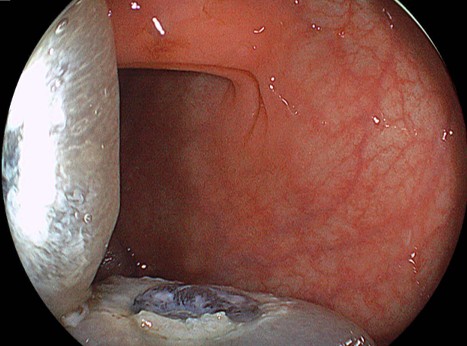

症例1:他院から日帰り内視鏡切除目的で紹介された症例。盲腸に20mm大の平坦な病変を認めます。LST-NG(flat-elevated type)に分類されます。拡大内視鏡では「がん」を疑うVI型ピットパターンを認めませんでした。腺腫病変と考えました。5mm程度の近傍に憩室を合併しております。無条件で内視鏡的粘膜下層剥離術(ESD)を適応している施設も多いかと思います。しかし、このような病変は、線維化(:粘膜下層の線維が密に増生していること、しばしば内視鏡治療の困難性を引き起こします)がなければESDの適応などないのです。当院では、内視鏡的粘膜切除術(EMR)により平坦な病変であっても30mm弱程度までは適応としていることが多いです。最終病理診断:高異型度腺腫で切除断端陰性で治癒切除(ちゆせつじょ:取り切れて治っていること)でした。術後も偶発症を認めませんでした。

粘膜下層に局注して、挙上がえられれば内視鏡的粘膜切除術(EMR)の適応となります。

スネアリングするための、適切な場を設定されました。あとはスネアリングするだけです。